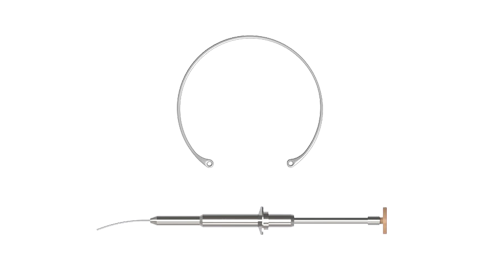

Eyebright Medical Technology (Beijing) Co., Ltd. (“Eyebright Medical”; SH Stock Code: 688050) is a National High-tech Enterprise and state-level technologically advanced "Little Giant" enterprises, located in Zhongguancun Science and Technology Park, Beijing, China. The Company is an innovation-driven ophthalmic medical device manufacturer. Its balanced product portfolio spans three major areas of the ophthalmic field: surgical treatment, myopia management, as well as consumer vision care. Anchored by its three core product categories - intraocular lenses, orthokeratology lenses, and soft contact lenses - the company has strategically expanded its product pipeline to cover the full life cycle of eye health solutions. Eyebright Medical is striding into a world-leading medical enterprise on behalf of China’s "Intelligent Manufacturing" power.